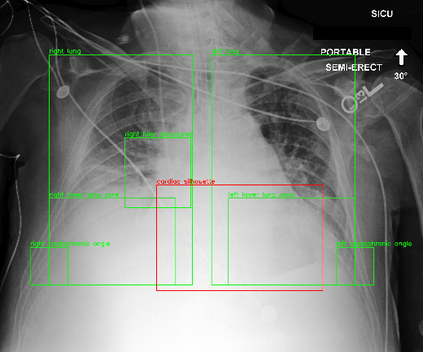

Despite the progress in utilizing deep learning to automate chest radiograph interpretation and disease diagnosis tasks, change between sequential Chest X-rays (CXRs) has received limited attention. Monitoring the progression of pathologies that are visualized through chest imaging poses several challenges in anatomical motion estimation and image registration, i.e., spatially aligning the two images and modeling temporal dynamics in change detection. In this work, we propose CheXRelNet, a neural model that can track longitudinal pathology change relations between two CXRs. CheXRelNet incorporates local and global visual features, utilizes inter-image and intra-image anatomical information, and learns dependencies between anatomical region attributes, to accurately predict disease change for a pair of CXRs. Experimental results on the Chest ImaGenome dataset show increased downstream performance compared to baselines. Code is available at https://github.com/PLAN-Lab/ChexRelNet

翻译:尽管在利用深层学习实现胸前射线解释和疾病诊断任务自动化方面取得了进展,但连续的胸前X射线(CXRs)之间的变化受到的注意有限。通过胸前成像可视化的病理进展监测在解剖运动估计和图像登记方面带来了若干挑战,即在空间上对两种图像进行匹配,在变化检测中模拟时间动态。在这项工作中,我们提议CheXRelNet,这是一个神经模型,可以跟踪两个CXRs之间的纵向病理变化关系。CheXRelNet包含当地和全球的视觉特征,利用图像间和图像内解剖学信息,并学习解剖区域属性之间的依赖性,准确预测两对CXR的疾病变化。Chest ImaGenome数据的实验结果显示,与基线相比,下游的性能有所增加。代码可在https://github.com/PLAN-Lab/CexRelNet上查阅。